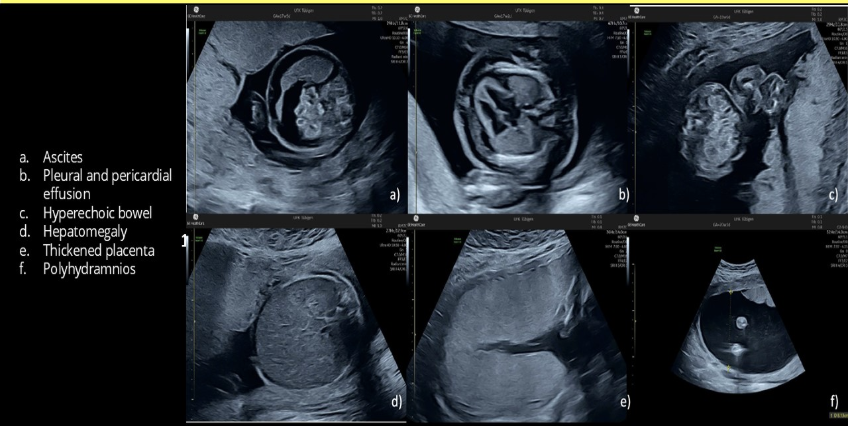

which is most likely to cause polyhydramnios, fetal ascites, and hepatomegaly

.

a) parvovirus infection

b) IUGR

c) potter syndrome

d) autosomal recessive PKD